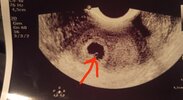

Ostatnią miesiączkę miałam 21.10, dziś byłam na USG (wgl apki wychodzi, że to 5t5d) doktor powiedział że na USG widzi pęcherzyk ale zarodka jeszcze brak, nic nie wspomniał o tym ciałku żółtym i trochę się martwię. Wgl USG było przeprowadzone na odpierdziel, ja byłam pewna że dziś będzie już zarodek, trochę mnie ta informacja zasmuciła i nie zapytałam co to jest właściwie na tym zdjęciu. Może wiecie? No i przede wszystkim to jest ok, że nie widać jeszcze zarodka? Odchodzę już od zmysłów